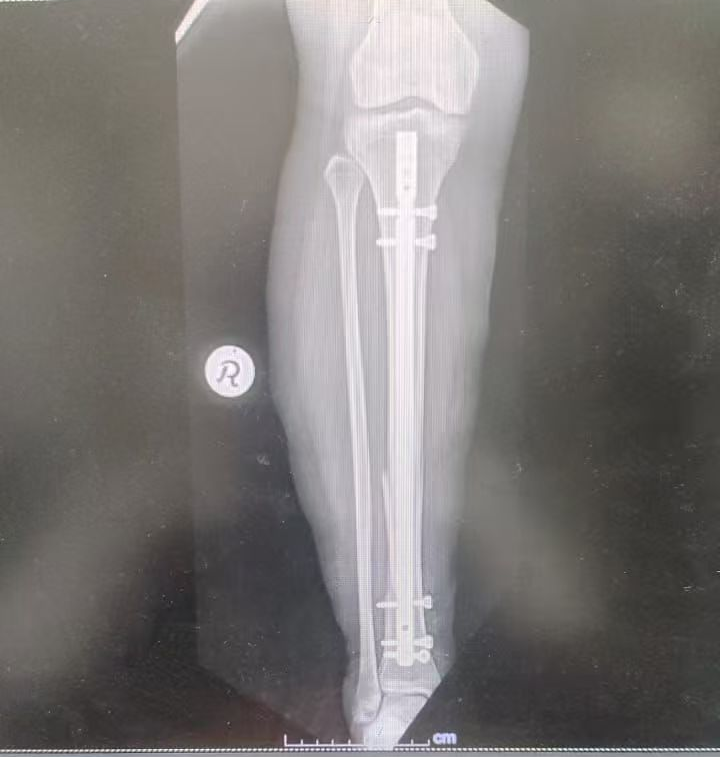

Figure 3: Final X-ray

Figure 4: Final X-ray